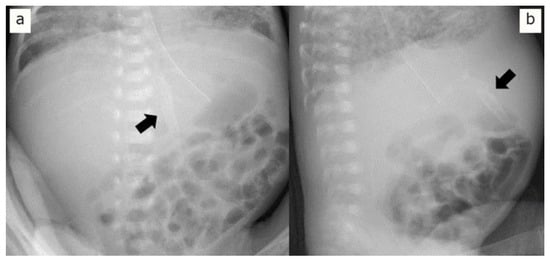

2. Case Presentation